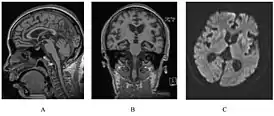

![]() У человека с наследственным прионным заболеванием наблюдается атрофия мозжечка. Это очень типично для синдрома ГШШ | |